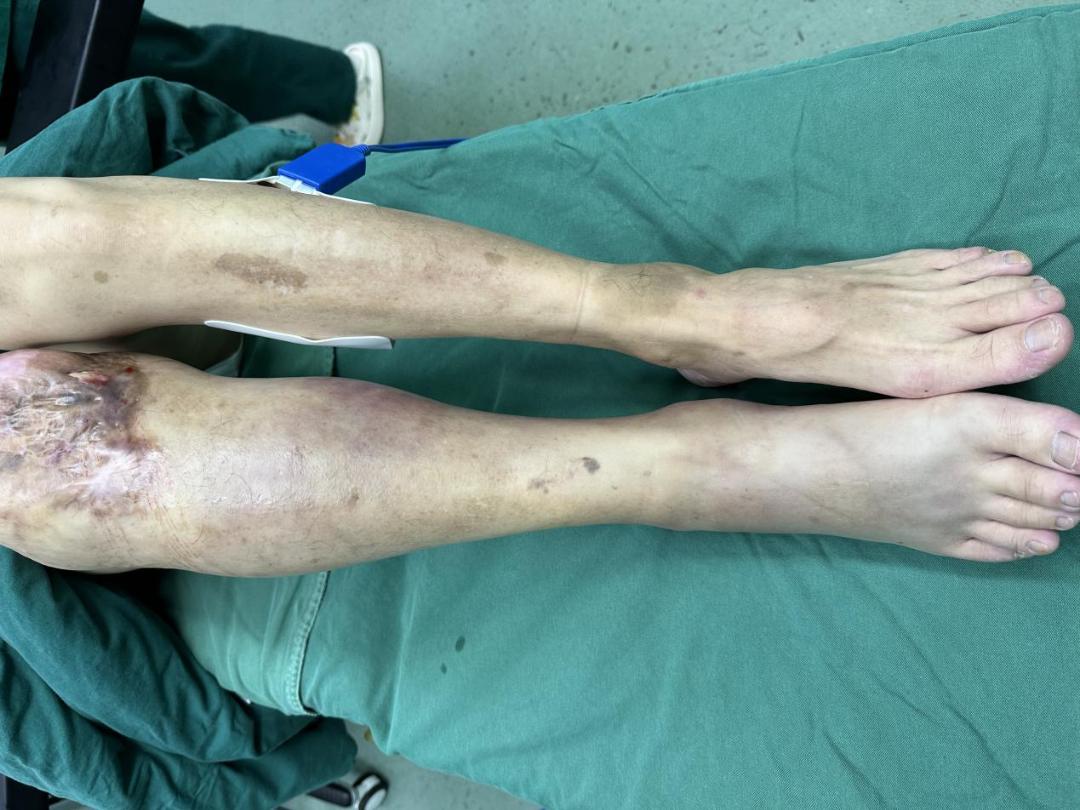

小蘇被送到我院時已高燒、精神萎靡,且血壓低,出現(xiàn)膿毒性休克、多臟器功能不全。從右背到右大腿腫脹明顯,皮膚發(fā)烏,局部出現(xiàn)血皰,肢體冰涼,右下肢廣泛的缺血性壞死,情況危急!燒傷創(chuàng)面修復(fù)科魏智藝醫(yī)生仔細(xì)檢查后考慮傷情緊急,立即給予補(bǔ)液抗休克、抗感染、臟器功能維護(hù)等一系列治療,并急診對右下肢進(jìn)行搶救性手術(shù)。

8月中旬,小蘇在海邊玩耍時,不小心被礁石劃破腳背。回家后,他馬上到當(dāng)?shù)蒯t(yī)院進(jìn)行消毒、包扎,并點(diǎn)滴抗感染。然而,治療了四五天未見緩解,腳背越來越腫,皮膚開始發(fā)黑、流膿。診所醫(yī)生擔(dān)心是創(chuàng)傷弧菌感染,建議立即轉(zhuǎn)診大醫(yī)院。

817日,小蘇到達(dá)我院就診時,已是高燒不退,病情嚴(yán)重。燒傷創(chuàng)面修復(fù)科醫(yī)護(hù)團(tuán)隊為小蘇實(shí)施緊急手術(shù),進(jìn)行清創(chuàng)、植皮,治療順利。